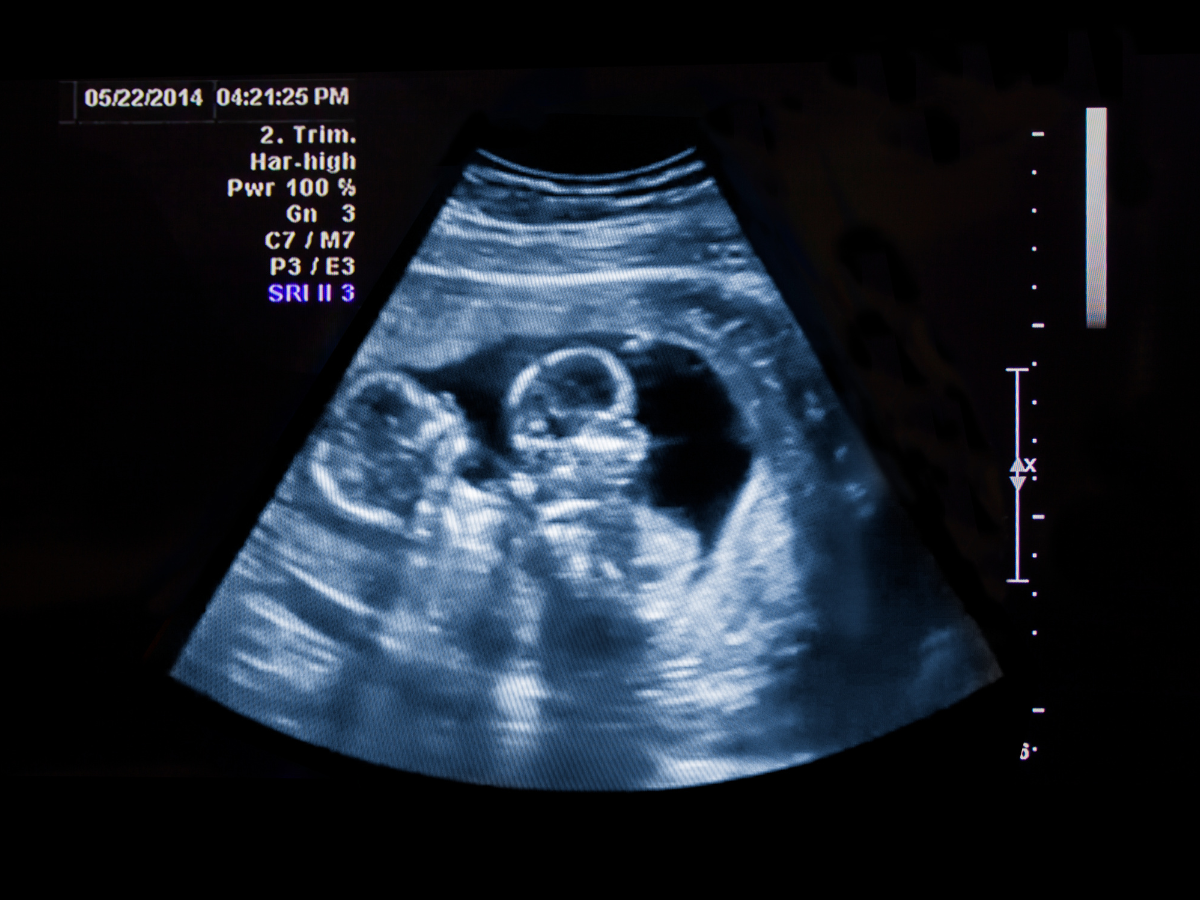

Ultrasound Scan: Typically, the first indication of twins occurs during an ultrasound scan, usually performed in the first trimester. This scan allows healthcare providers to visualize the developing embryos and identify multiple gestational sacs or distinct heartbeats, indicating the presence of twins.

Scanning Begins: The technician or sonographer will gently move the transducer over your abdomen. Sound waves emitted by the transducer bounce off your internal structures, including your babies, and create images on a monitor.

Examining the Twins: During the scan, your healthcare provider will carefully examine each baby's development. For fraternal twins, they'll look for separate placentas and amniotic sacs, which indicate each baby's unique environment. In the case of identical twins, they may check for signs like a shared placenta or sac.

Assessing Health and Growth: The ultrasound provides valuable insights into your twins' growth patterns, checking measurements like head circumference, abdominal circumference, and femur length. This information helps monitor their health and development.

Weeks 18-22: Detailed Anatomy Scan As you progress into the second trimester, typically between weeks 18 to 22, you'll undergo a comprehensive anatomy scan. This detailed ultrasound examines your twins' growth, checking their organs, limbs, and overall development. Your healthcare provider will assess the health of each baby, the placenta(s), and the amniotic fluid levels. It's an exciting time as you get to see your babies' features and possibly find out their genders if you choose.